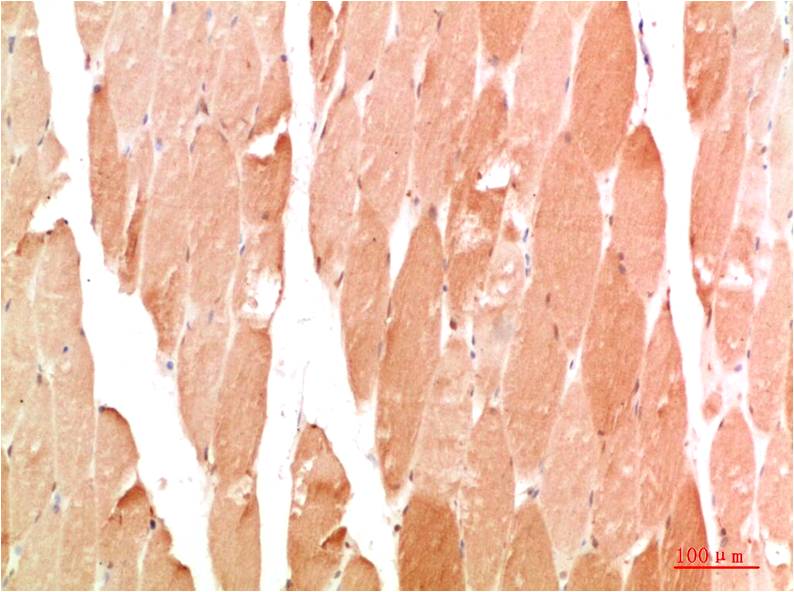

IkB α Rabbit Polyclonal Antibody

Applications :WB, IHC

| Recommended dilutions: | WB 1:500-2,000 IHC 1:50-300 |